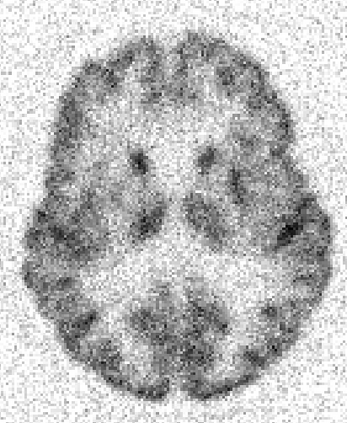

Due to various physical degradation factors and limited counts received, PET image quality needs further improvements. The denoising diffusion probabilistic models (DDPM) are distribution learning-based models, which try to transform a normal distribution into a specific data distribution based on iterative refinements. In this work, we proposed and evaluated different DDPM-based methods for PET image denoising. Under the DDPM framework, one way to perform PET image denoising is to provide the PET image and/or the prior image as the network input. Another way is to supply the prior image as the input with the PET image included in the refinement steps, which can fit for scenarios of different noise levels. 120 18F-FDG datasets and 140 18F-MK-6240 datasets were utilized to evaluate the proposed DDPM-based methods. Quantification show that the DDPM-based frameworks with PET information included can generate better results than the nonlocal mean and Unet-based denoising methods. Adding additional MR prior in the model can help achieve better performance and further reduce the uncertainty during image denoising. Solely relying on MR prior while ignoring the PET information can result in large bias. Regional and surface quantification shows that employing MR prior as the network input while embedding PET image as a data-consistency constraint during inference can achieve the best performance. In summary, DDPM-based PET image denoising is a flexible framework, which can efficiently utilize prior information and achieve better performance than the nonlocal mean and Unet-based denoising methods.